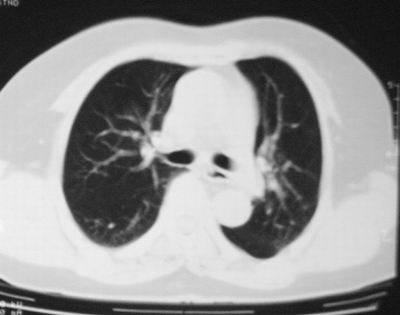

患者,女,64岁,4年前左腮腺"多形性"腺瘤手术治疗史.现复查胸部ct见左下肺块状影,该影与原左腮腺手术是否有联系?

本次复查胸部ct

左下肺软组织块影,有分叶、毛刺、空泡及胸膜牵拉征,左下肺周围性肺癌。

左肺下叶周围型肺癌,支持!(软组织肿块+分叶+毛刺+空泡+胸膜凹陷征)

左下肺软组织密度影,可见分叶,边缘可见毛刺征,胸膜增厚,强烈要求左下肺周围型肺癌

左下肺后基底段实性肿块,周围有毛刺,病变周围有肺气肿,与降主动脉间有条带状影相连,病灶4年前查体发现,纵隔内未见肿大淋巴结。考虑.肺隔离症,建议增强扫描与周围型肺癌鉴别。